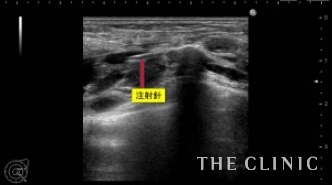

一つ一つヒアルロニダーゼ(ヒアルロン酸溶解剤)を注入して吸引していきます。